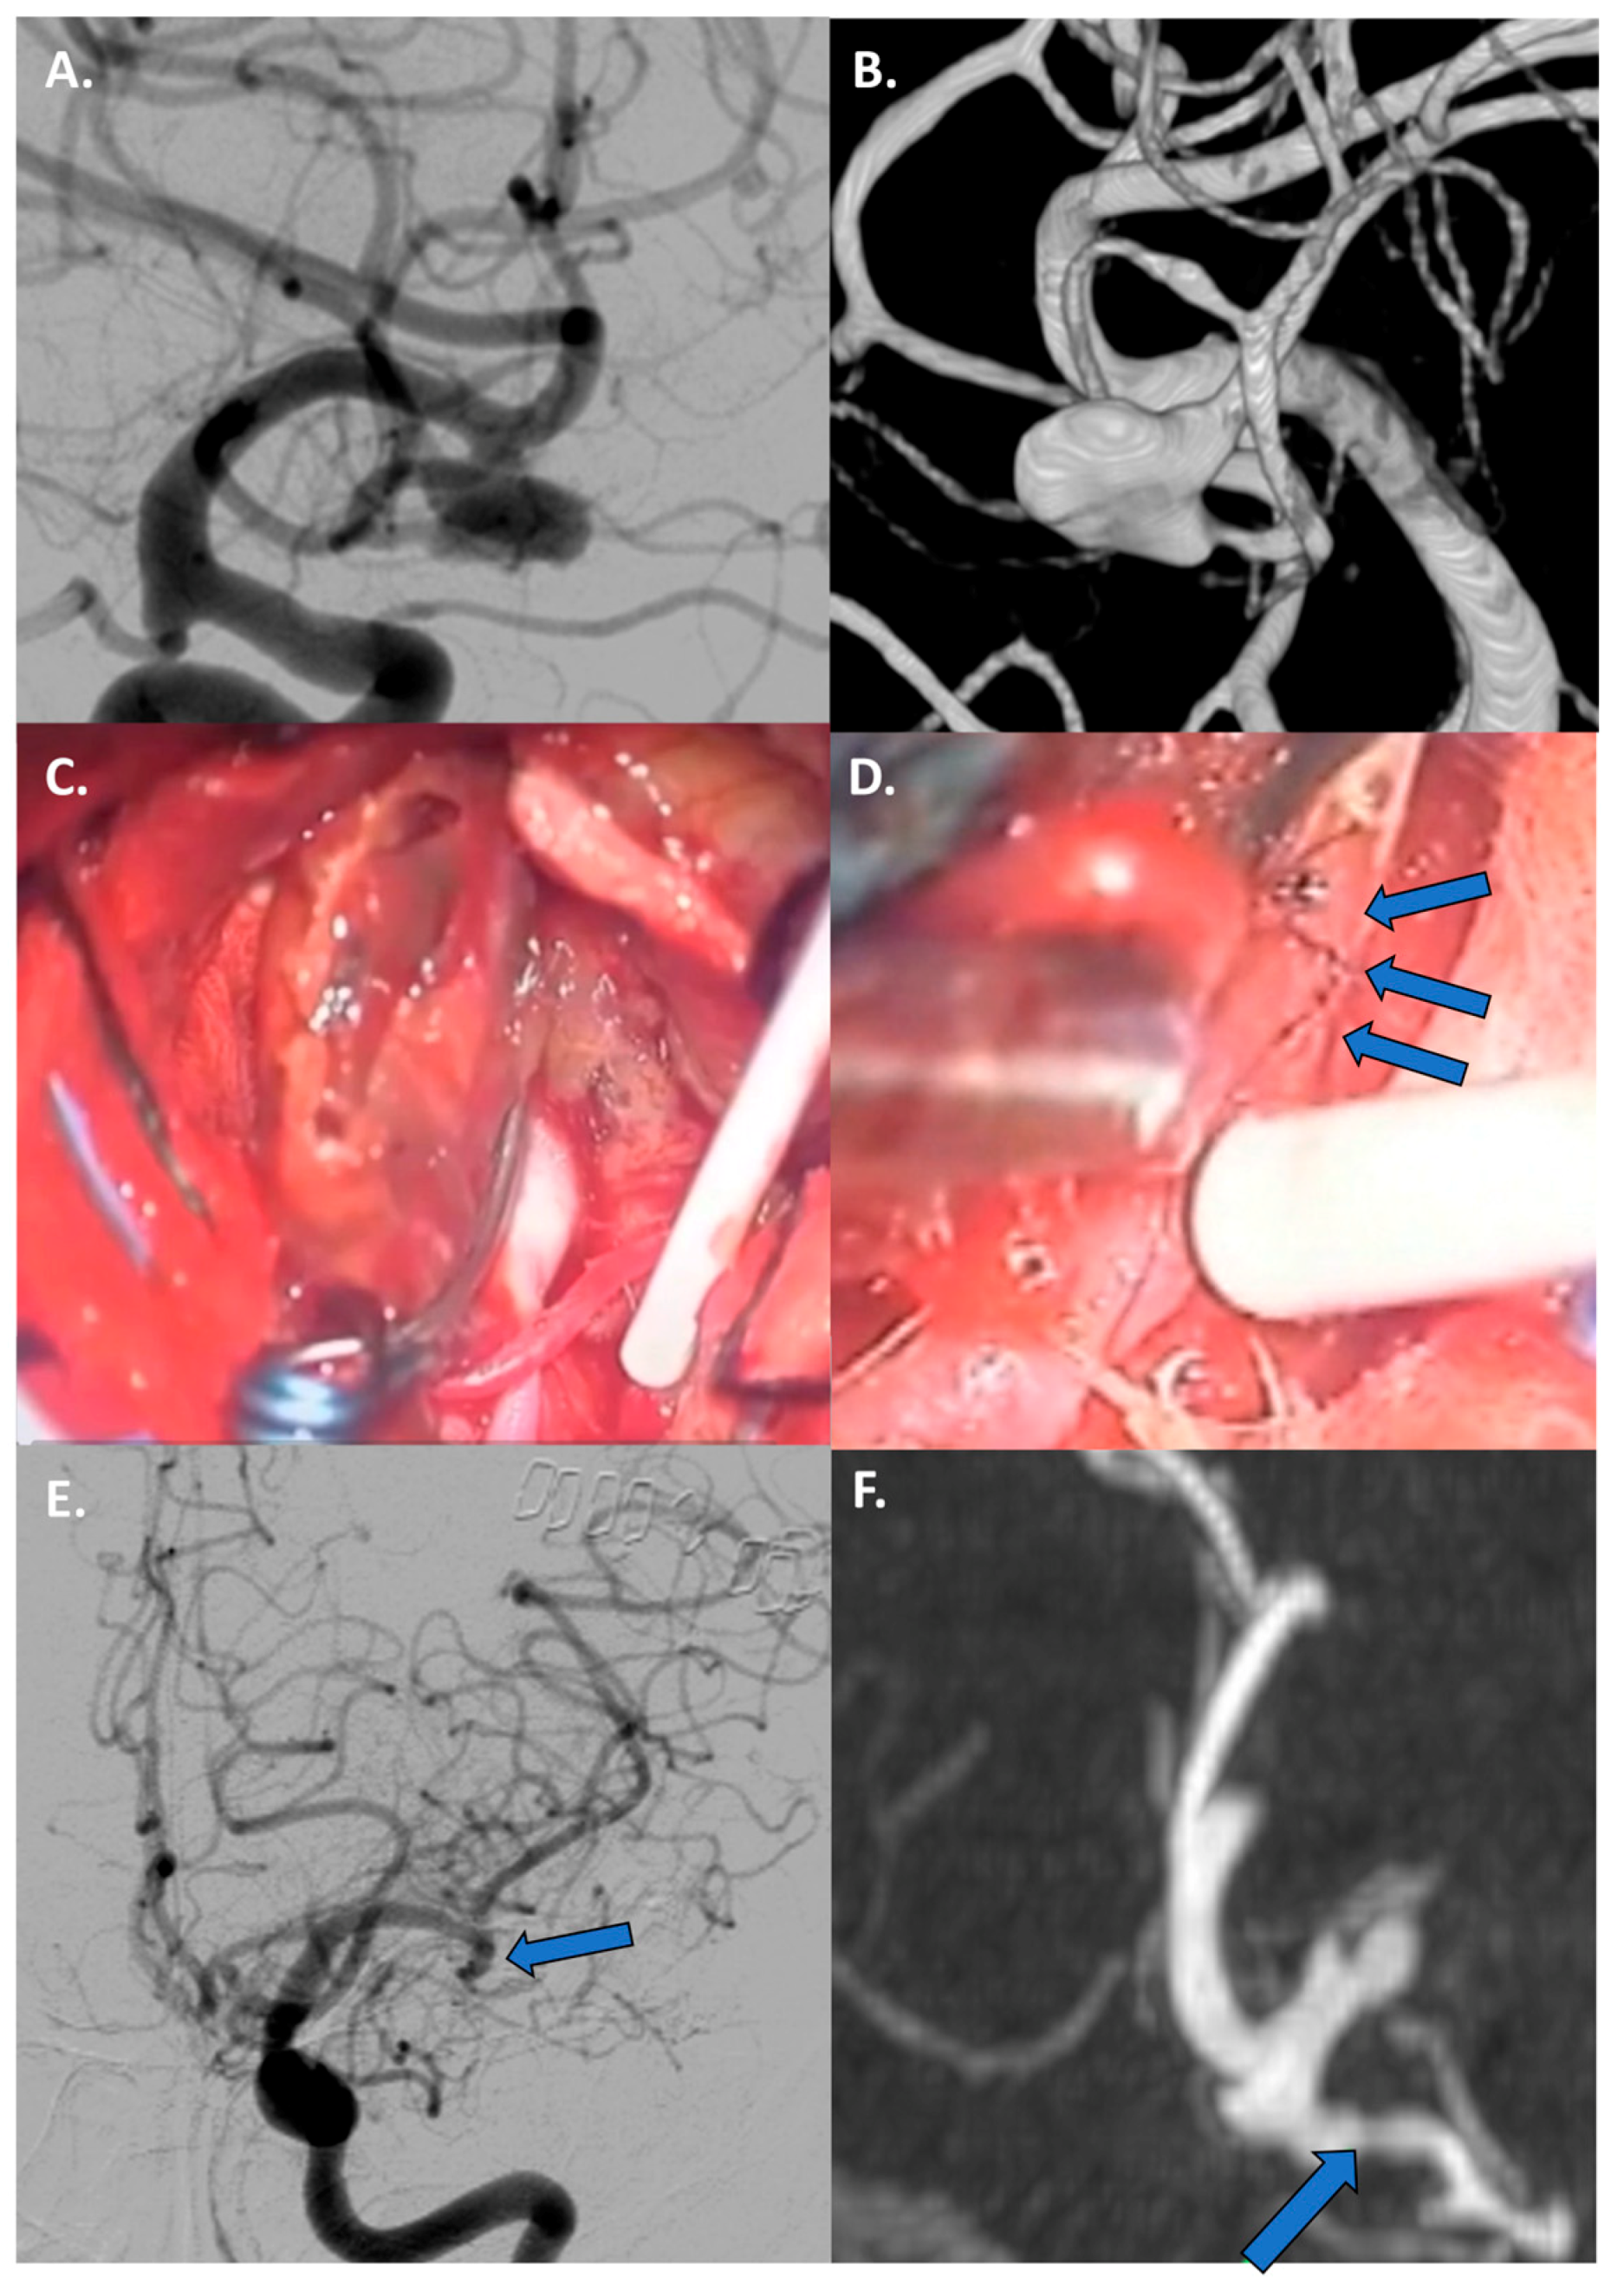

4.3.3. Thrombosed Aneurysm and/or Previously Treated Aneurysms